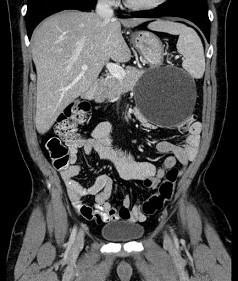

问题 关于假性胰腺囊肿,下列哪项是错误的 ( )

选项 A、可形成脓肿 B、继发于胰腺或上腹部外伤后 C、可形成胰源性腹水 D、无上皮细胞 E、多位于胰头部

答案 E